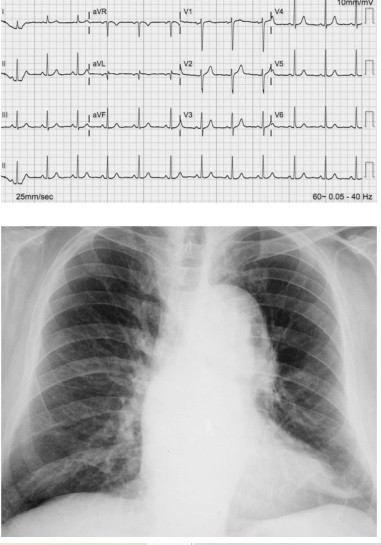

Uma paciente de 61 anos de idade compareceu à emergência com queixa de dor torácica. Havia três horas iniciou um quadro de precordialgia muito intensa do tipo lancinante e com irradiação para a região torácica dorsal. Ela tratava hipertensão arterial sistêmica com hidroclorotiazida 25 mg ao dia, irregularmente, havia 14 anos. Ao exame físico encontrava-se, acianótica, sudorética, com pressão arterial de 176 mmHg × 114 mmHg, saturação de oxigênio em ar ambiente de 93%, pulsos reduzidos em membros inferiores, ritmo cardíaco regular em dois tempos sem sopros, com ausculta pulmonar normal. O restante do exame físico foi normal. A dosagem das enzimas cardíacas (CK-MB massa e troponina) e os demais exames laboratoriais de rotina foram normais. Realizou um eletrocardiograma e uma radiografia de tórax que podem ser vistas a seguir.